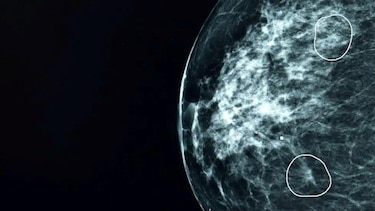

El equipo evaluó cómo el software de IA podría utilizarse para apoyar al personal sanitario en las mamografías de rutina de más de 10.000 mujeres, quienes además podrían recibir los resultados con mayor rapidez.

Puede detectar posibles áreas pequeñas y difíciles de observar en las mamografías que podrían pasar desapercibidas para el ojo humano.

El estudio sobre la detección del cáncer de mama, publicado en la revista Nature Cancer, reveló que podría aumentar la detección en un 10,4%.

"Me hicieron una tomografía y el médico especialista confirmó que el diagnóstico de la IA era correcto: había un pequeño tumor de grado 2, demasiado pequeño para ser detectado a simple vista".